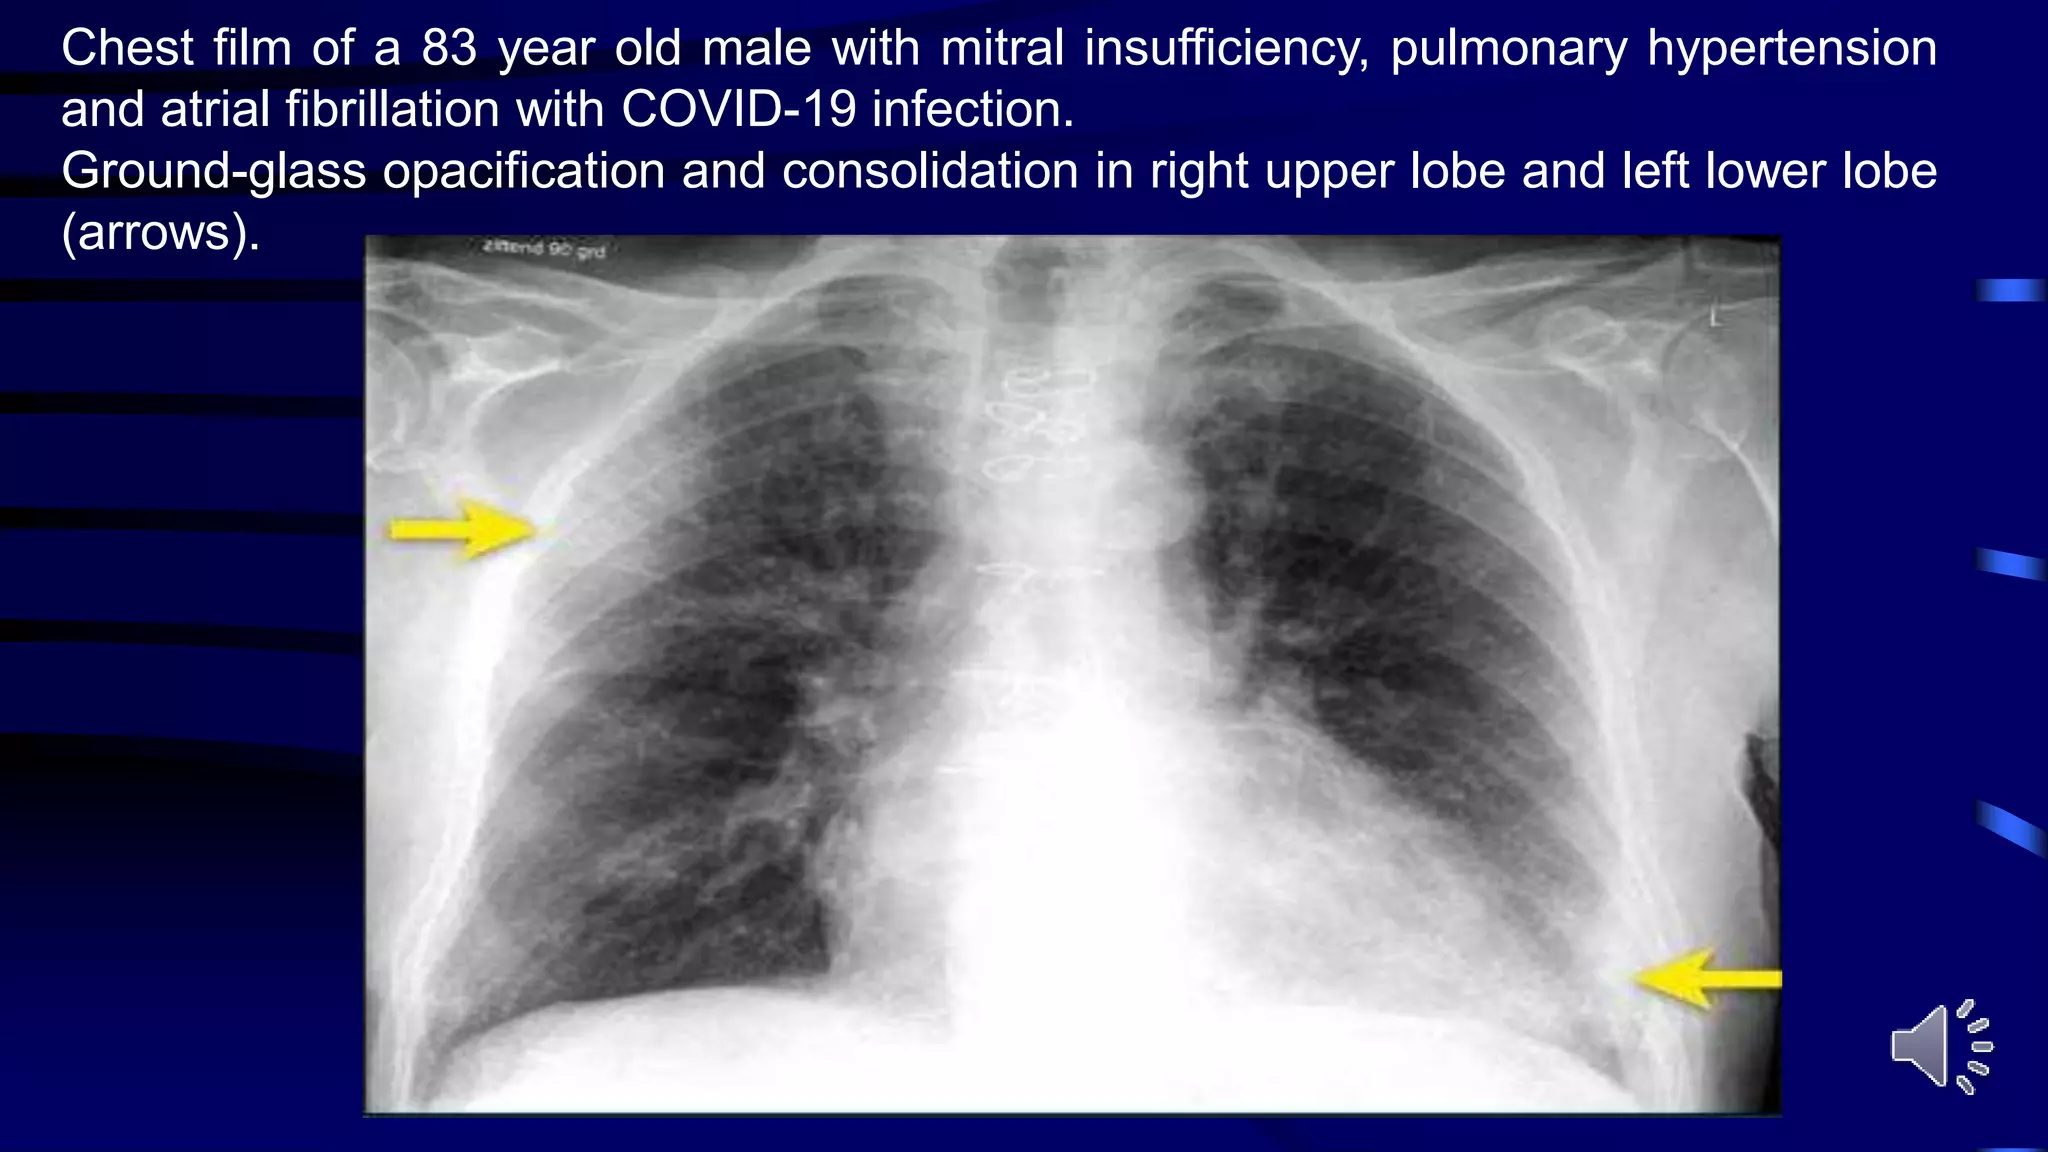

Chest film of a 83 year old male with mitral insufficiency, pulmonary hypertension

and atrial fibrillation with COVID-19 infection.

Ground-glass opacification and consolidation in right upper lobe and left lower lobe

(arrows).